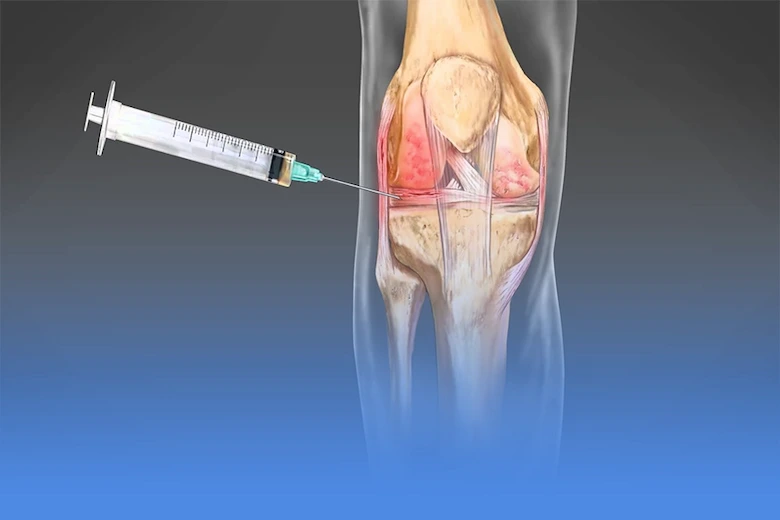

تزریقهای داخل مفصل زانو

در شرایطی که درد شدید باشد یا درمانهای اولیه پاسخ کافی ندهند، تزریق داخل مفصل میتواند گزینهای موثر باشد. تزریق کورتون معمولا برای کاهش درد و التهاب کوتاه مدت استفاده میشود، در حالی که تزریق اسید هیالورونیک به روان کاری مفصل کمک کرده و حرکت زانو را راحتتر میکند. روشهای بیولوژیک مانند تزریق PRP نیز با هدف ترمیم بافتها و کاهش درد به کار میروند. به طور کلی، انتخاب نوع تزریق بسته به شدت بیماری، سن بیمار و وضعیت مفصل توسط پزشک متخصص فیزیوتراپی تعیین میشود.